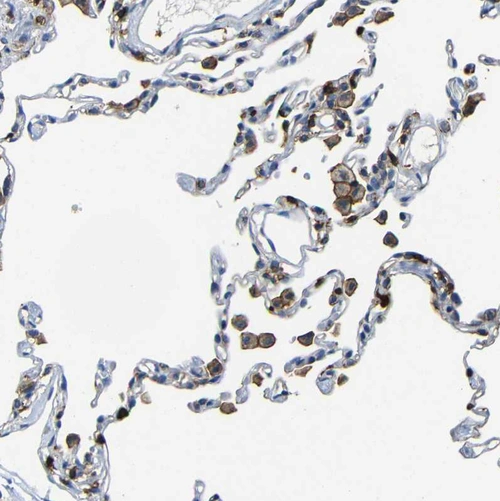

Immunohistochemistry analysis in human cerebral cortex and skeletal muscle tissues using HPA013796 antibody. Corresponding P2RY12 RNA-seq data are presented for the same tissues.